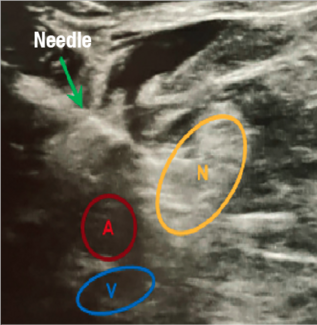

As ultrasound-guided injections become more common in podiatric practices to assist in diagnosis and therapeutic intervention, this author shares practical pearls and her experience.